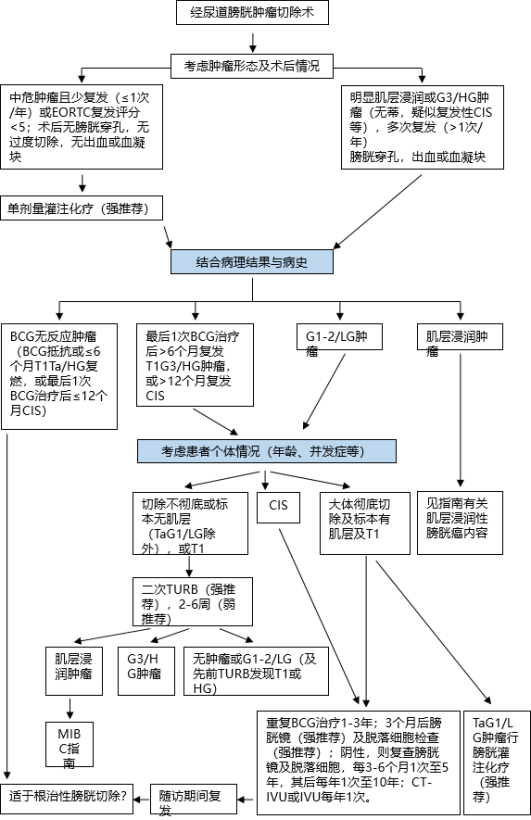

经尿道膀胱肿瘤切除术:

研究证实,切除的膀胱肿瘤标本中,逼尿肌组织的缺乏与肿瘤残留、早期复发及肿瘤分期被低估的风险显著相关。切除的膀胱肿瘤标本中,逼尿肌组织的存在是一项规定性的质量标准。

BCG治疗期间或治疗后复发低级别肿瘤,不属于BCG治疗失败。

BCG膀胱灌注治疗失败病例分类: